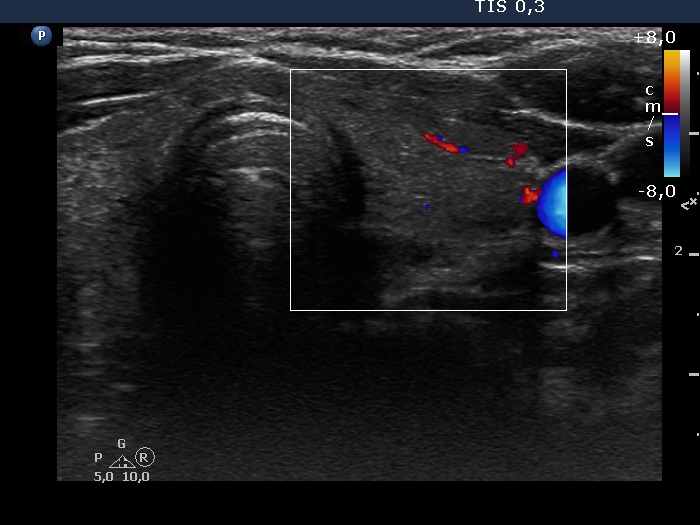

Right lobe, longitudinal scan

Left lobe, transverse scan, color Doppler mode. The vascularization is decreased.